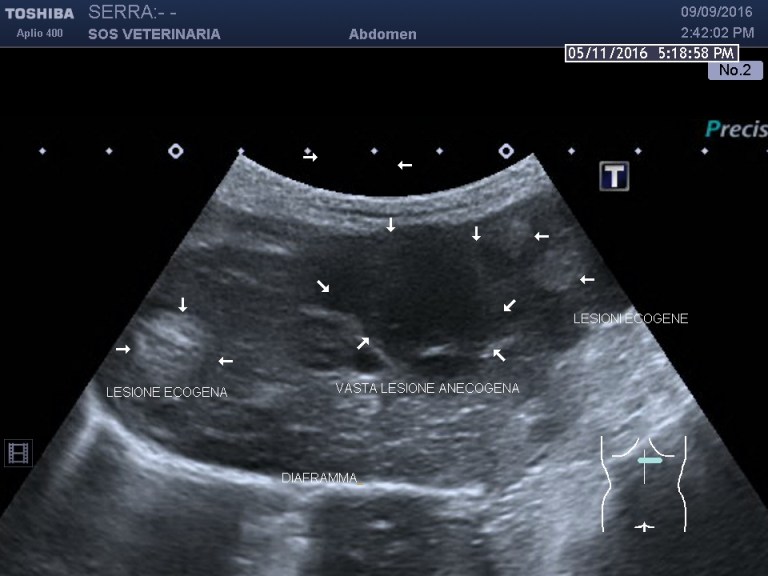

Gatta comune europea ,eta’ 5 anni ,improvvisa debolezza,vive in casa ,alla visita: mucose pallide,lieve distensione addome ,l’ecografia di base evidenzia emoperitoneo (versamento campionato) e due masse di alcuni centimetri ipoecogene peritoneali a profilo uniforme avascolari al color doppler , lesioni focali epatiche alcune molto demarcate ed ecogene altre consistenti in aree piu’ o meno demarcate con settori ane-ipoecogeni e settori ecogeni , demarcazione del profilo dei lobi nelle porzioni caudali meno definito.

sono evidenti lesioni focali avascolari (completa assenza di assunzione di contrasto) alcune non evidenziate all’esame B mode ,altre francamente ecogene in B mode ,lesioni dunque necrotiche demarcate purtroppo neoplastiche altamente suggestive di emangiosarcoma .